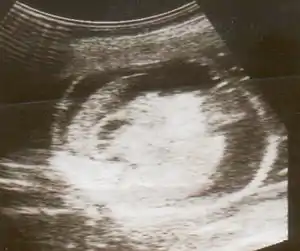

| An ultrasound showing a fetus with Hydrops fetalis | |

Hydrops fetalis can be diagnosed and monitored by ultrasound scans. An official diagnosis is made by identifying excess serous fluid in at least one space (ascites, pleural effusion, of pericardial effusion) accompanied by skin edema (greater than 5 mm thick). A diagnosis can also be made by identifying excess serous fluid in two potential spaces without accompanying edema. Prenatal ultrasound scanning enables early recognition of hydrops fetalis and has been enhanced with the introduction of MCA Doppler.[5]